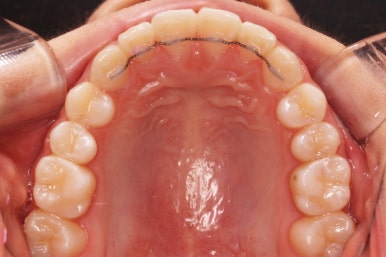

따라서 교정치료에 앞서 위턱은 가로로 넓혀주는 악궁확장장치(RPE)를 시행하기로 했습니다.

아래쪽이 더 시급하므로 브라켓 부착을 하여 가지런히 하기 시작했고 위쪽은 악궁확장장치를 입천장에 하여 위턱뼈를 가로로 넓혀주기 시작합니다.

악궁확장장치는 총 4-6개월 정도 부착하고 있으며 그 이후에는 입안에서 제거하게 됩니다.

윗니에도 이제 장치를 모두 붙였습니다. 아래쪽은 어느 정도 가지런해지고 나면 부족한 자리를 만들어주기 시작합니다.